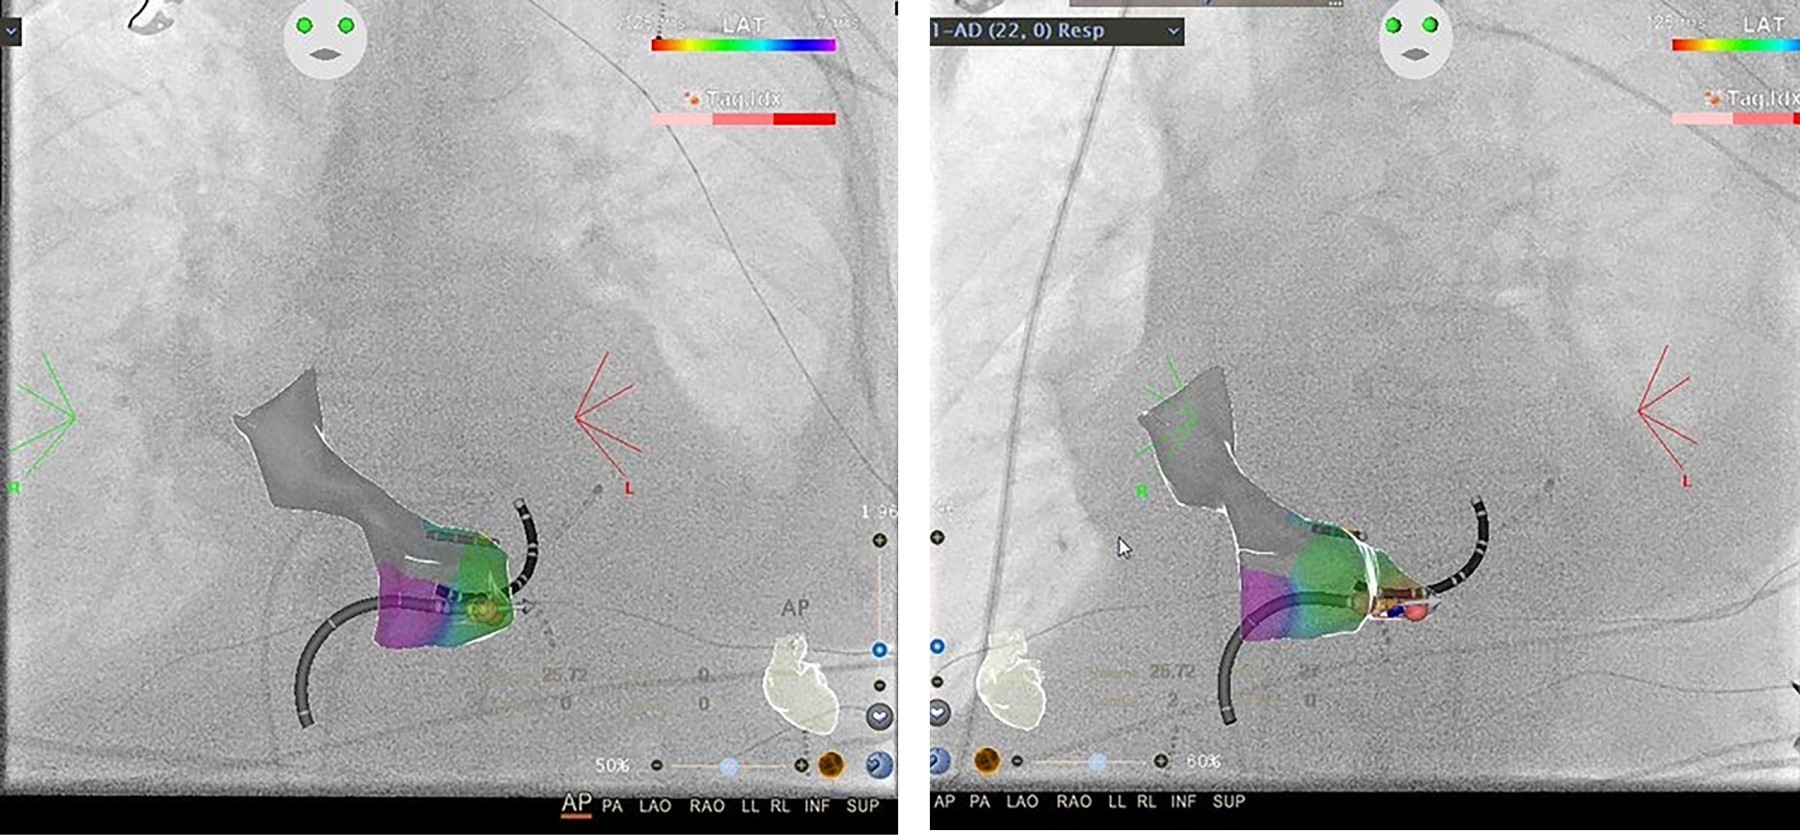

Reducción de la exposición a la radiación en un laboratorio de electrofisiología con el módulo CARTO-UNIVU™

La ablación por radiofrecuencia es una técnica eficaz y segura para el tratamiento de diferentes tipos de arritmias. La ablación por radiofrecuencia se realiza mediante fluoroscopia, una guía de navegación estándar, que está asociada con la exposición a la radiación y sus efectos nocivos bien reconocidos para los pacientes y para el personal de laboratorio. En la última década, los sistemas de mapeo electroanatómico han experimentado un fuerte desarrollo. A pesar de sus indiscutibles ventajas, no incluyen información obtenida por fluoroscopia en tiempo real. El módulo CARTO-UNIVU™ aborda esta importante limitación, ya que combina imágenes de fluoroscopia con el mapeo eletroanatómico tridimensional (3D) en una sola vista 3D, lo que permite una reducción pronunciada de la exposición a la radiación. Presentamos cuatro casos de nuestra primera experiencia en un solo centro con el nuevo módulo CARTO-UNIVU™.

Figura 1